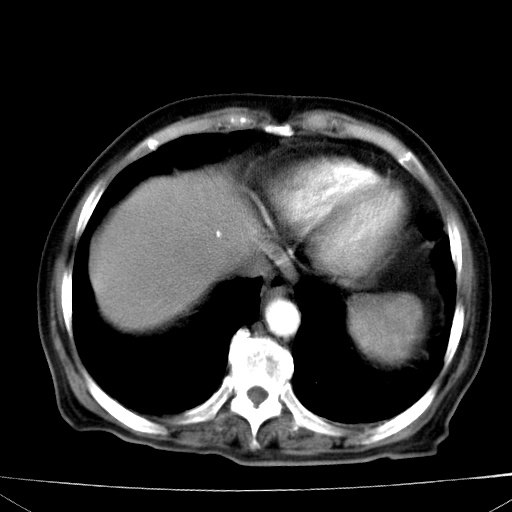

网站人气太旺!昨天的帖子就沉到海底,只好再发贴!ct18338:女 78岁,肝胆病变,已增强,再会诊!原帖链接:http://www.radida.com/bbs/forum.php?mod=viewthread&tid=50032

1)考虑胆囊癌侵犯肝脏并肝门区、腹膜后及右侧膈角后淋巴结转移。2)肝左叶近肝顶部囊肿。3)肝左叶肝内胆管结石。4)左肾近下极囊肿。